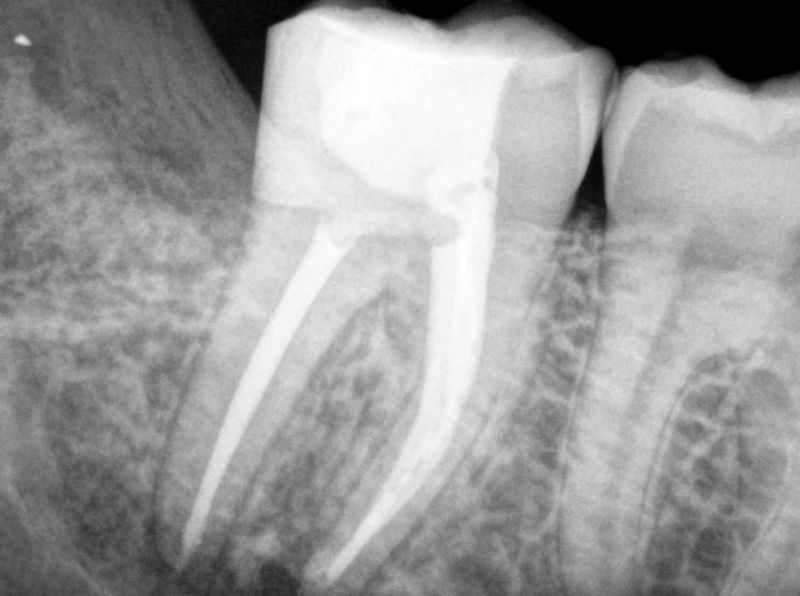

Ендодонцијата е гранка на стоматологијата која се занимава со третман и превенција на болести и состојби што ја зафаќаат забната пулпа и околните ткива. Забната пулпа е меко ткиво во внатрешноста на забот, составено од нерви, крвни садови и сврзно ткиво. Ендодонтскиот третман најчесто подразбира терапија на коренскиот канал, чија главна цел е да се спасат забите кои се сериозно оштетени или инфицирани.

Терапијата на коренскиот канал е најчестата ендодонтска процедура. Процесот вклучува:

Во одредени случаи, кога конвенционалниот третман на коренскиот канал не е доволен, може да се изведе ендодонтска хирургија. Најчеста процедура е апикотомија — хирургија на врвот на коренот, при што се отстранува врвот на коренот заедно со инфицираното ткиво. Овој процес помага да се елиминира изворот на инфекцијата и да се зачува забот.